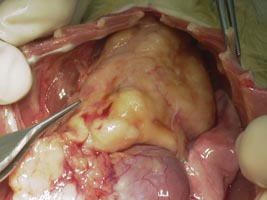

副腎腫瘍と悪性リンパ腫で死亡したフェレットの解剖写真です。貴重な画像です。

| H13.7月 | 副腎摘出手術。血管と癒着しているので左側の一部のみ摘出。組織検査はせず。 |

| H14.3月 | 死亡 解剖の結果、肺・肝臓・膵臓・副腎に転移。悪性リンパ腫との診断。 |

核小体明瞭な不整形の核と乏しい胞体を有するリンパ球類似の異型細胞が既存の組織を置換するようにびまん性に増殖している。